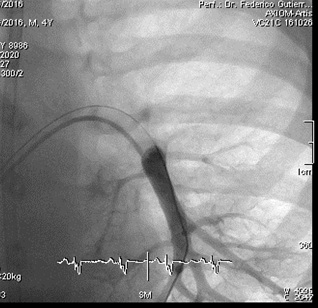

Catheterization was naturally indicated for managing his condition. We first performed an ultrasonic evaluation of his femoral veins to ensure they had at least a 3 mm axial diameter. After securing vascular access, angiographic verification of the right femoral vein patency and diameter was performed. We conducted a standard diagnostic hemodynamic catheterization under fluoroscopic control in a biplane system (Artis Zee, Siemens®) with a low dose protocol. Then, pump injection with diluted contrast (0.5 ml of isosmolar contrast per kg of body weight, diluted with isotonic saline solution in a 70% contrast to 30% saline ratio) into the left pulmonary artery was achieved with biplanar acquisition at 15 images per second (Figures 1 & 2). This process was to examine the left lung pulmonary arterial architecture to find an ideal implantation site, requiring a length of at least 30 mm with initial and final diameters of 7 and 5 mm, respectively, and a bifurcation pattern showing branches larger than 3 mm in diameter. Once the target site was selected, the angiographic catheter was exchanged over a conventional 0.035 guidewire, which served as a support for successive dilations of the venous access point until the 12 F introducer advanced without resistance. A multipurpose 5F catheter was then advanced over the guidewire, followed by a 0.35 hydrophilic guidewire to position the catheter in the selected segment. After removing the hydrophilic guidewire, a small manual contrast injection was performed to evaluate the distal anatomy before advancing a 0.018” guidewire through the catheter, ensuring the floppy segment did not distort or angle and that a non-floppy portion was present at the device implantation site. With these considerations meticulously observed, and the catheter removed, the catheter housing the CardioMEMS was advanced, ensuring smooth and natural progression until reaching the destination and proceeding with its release. Following this, the catheter was removed, and the previous multipurpose catheter was reinserted to a position proximal to the device's release point. A manual contrast injection was then performed through the catheter via a Y-connector without removing the guidewire, and biplanar images were acquired to assess the occupied volume of the device, its loops, and any potential interference with the distal filling of that branch or collateral vessels. High-quality pulmonary pressures were obtained through CardioMEMS®, so the procedure was concluded without any problems related to the device or vascular access. Successful monitoring of the pulmonary pressures facilitated the management of this challenging patient, and a heart transplant was successfully performed 13 months later. The surgery required extensive manipulation of the patient's thorax, which, as evidenced in radiographs taken in the following days, led to displacement of the device that did not interfere with measurements. The patient underwent subsequent catheterizations for post-transplant protocolized control without complications in vascular access, performed through the same right femoral vein. On two occasions, an excellent correlation was observed between the invasive measurements of pulmonary pressures and the results from the CardioMEMS check. During a recent catheterization, within the regular control indications with the patient weighing 28 kg, this correlation was confirmed, and an angiography was performed on the left pulmonary branch showing the arterial vascular architecture (Figures 3 & 4). Despite the displaced device, there is no interference or obstruction to the permeability of the lobar and sub segmental branches in angiography nor in pressures distal or proximal and an excellent correlation was obtained between invasive (Figure 5) and CardioMEMS® measurements (Figure 6). The procedure confirmed the permeability of the pulmonary branches, reaffirming the utility of the device for continuous and non-invasive monitoring in a pediatric context.

Figure 3: Posteroanterior angiography of left inferior lobar pulmonary artery 4 years post-CardioMEMS® Implantation.